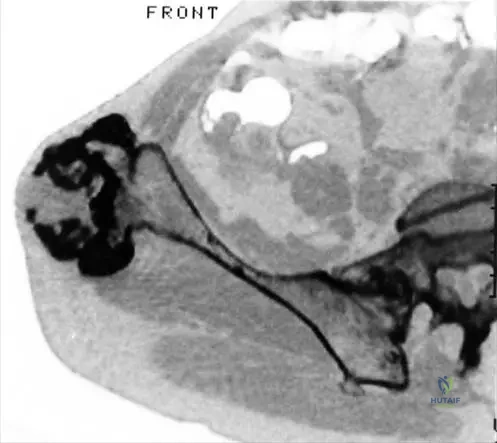

Question 27

A

A 35-year-old male presents with a slowly growing mass on the posterior aspect of his distal femur. Radiographs reveal a heavily mineralized mass on the surface of the bone with a clear cleavage plane from the underlying cortex and no apparent medullary involvement. A CT scan confirms the absence of cortical or medullary continuity between the mass and the parent bone.

View Answer & Explanation

Correct Answer: C

Rationale: Parosteal osteosarcoma typically presents as a heavily mineralized mass on the surface of the bone, most commonly on the posterior aspect of the distal femoral metaphysis, with no cortical or medullary continuity between the mass and the parent bone. This description perfectly matches the clinical vignette and radiographic findings. Conventional osteosarcoma is typically intramedullary and destructive. Periosteal osteosarcoma is a surface tumor but usually diaphyseal, partially mineralized, and may show malignant periosteal new bone formation. High-grade surface osteosarcoma is also on the surface but often shows more aggressive cortical involvement and incomplete mineralization. Chondrosarcoma would typically show chondroid matrix mineralization, not dense osteoid. The image (Fig. 8.69 a–c) clearly illustrates a parosteal osteosarcoma with its characteristic appearance.